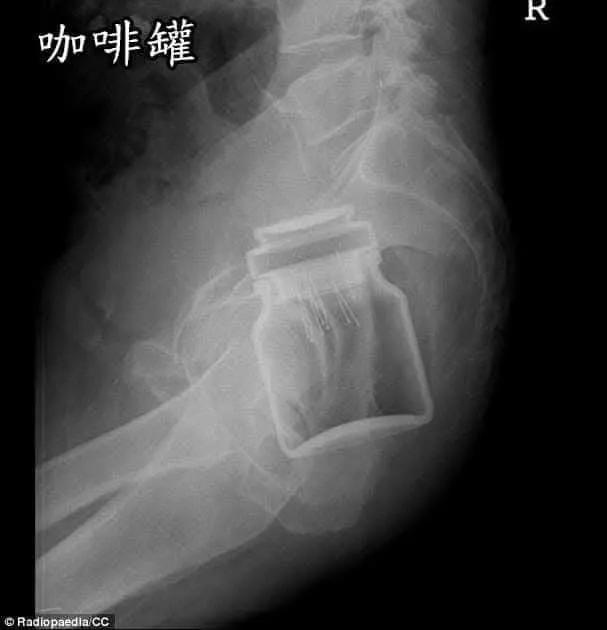

醫生公開「年度直腸內最怪案例」

醫師“衛教宣導”:拜託大家,屁眼是“消化器官”不是“性器官”,請不要為了“性樂趣

”,亂塞異物進入肛門!謝謝!!

https://i.imgur.com/mSqSfBP.jpeg 咖啡罐

![[圖]](https://imgur.disp.cc/4d/mSqSfBP.jpeg)